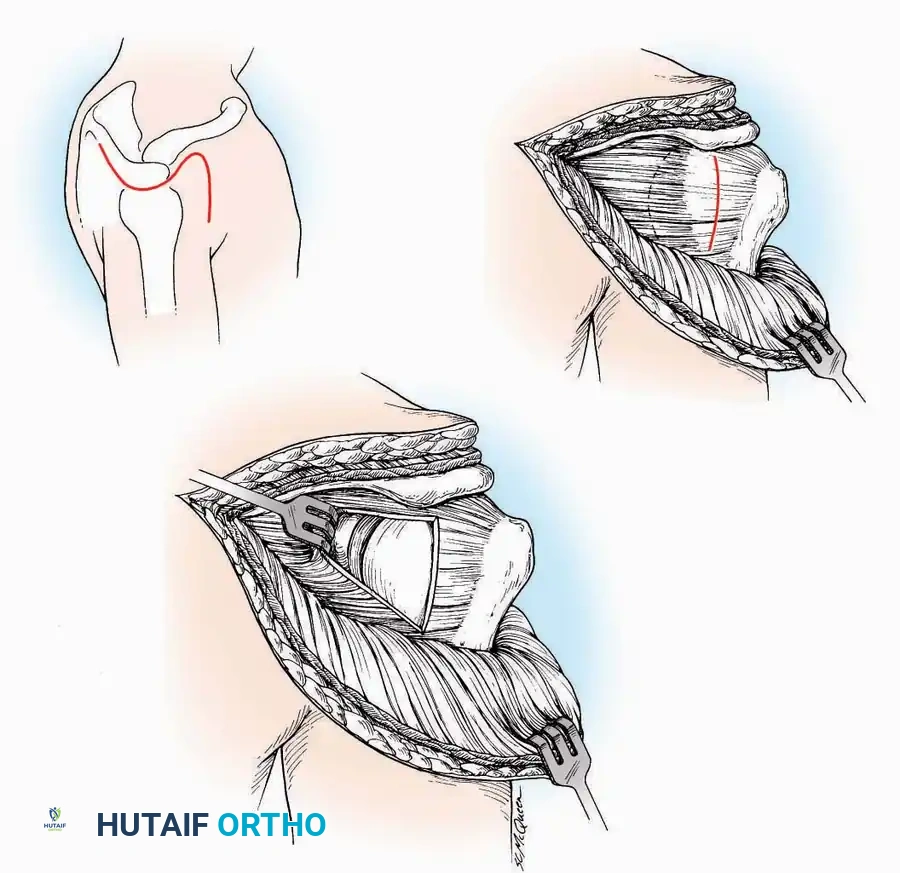

Anterolateral Approach

The anterolateral approach is widely considered the "universal incision" for the foot and ankle. It provides unparalleled access to the ankle joint, the talus, and the majority of the tarsal articulations, while safely avoiding the major anterior neurovascular bundle. The only tarsal joints inaccessible via this route are the naviculocuneiform joints (specifically the medial and intermediate).

Indications: Total talectomy, triple arthrodesis, ankle arthrodesis, and open reduction of complex talar neck fractures.

Surgical Technique:

* Incision: Begin over the anterolateral aspect of the leg, medial to the fibula and 5 cm proximal to the ankle joint line. Carry it distally over the joint, crossing the anterolateral aspect of the talar body and the calcaneocuboid joint, terminating at the base of the fourth metatarsal.

* Superficial Dissection: Incise the superficial fascia and the superior and inferior extensor retinacula down to the periosteum of the tibia and the ankle joint capsule.

* Vascular Ligation: This trajectory usually requires the identification and ligation of the anterolateral malleolar and lateral tarsal arteries.

* Nerve Protection: Retract the skin edges carefully. Identify and protect the intermediate dorsal cutaneous branches of the superficial peroneal nerve (SPN), which frequently cross the distal aspect of this incision.

* Muscle Management: Identify the origin of the extensor digitorum brevis (EDB) muscle on the lateral calcaneus. Divide it in the direction of its fibers, or detach its origin entirely and reflect it distally to expose the subtalar and calcaneocuboid joints.

* Deep Exposure: Retract the extensor digitorum longus (EDL) tendons, the dorsalis pedis artery, and the deep peroneal nerve (DPN) medially. Incise the anterior ankle capsule to expose the tibiotalar joint.

* Tarsal Exposure: Expose the talonavicular joint by dissecting deep to the extensor tendons and incising its capsule transversely. Continue laterally through the capsule of the calcaneocuboid joint. By excising the fat pad within the sinus tarsi (lateral and inferior to the talar neck), the posterior facet of the subtalar joint is brought into direct view.